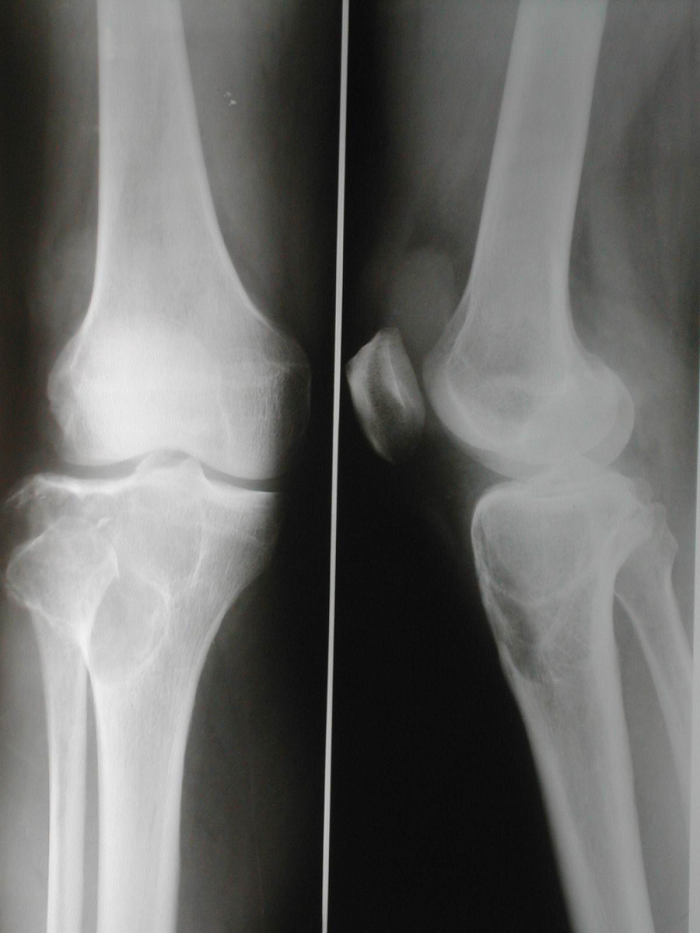

1.X线特点

发生于长骨的病变X线片通常表现为膨胀性、偏心性的溶骨性破坏,有时呈肥皂泡样改变。一般无骨膜反应骨生成。病变主要累及骨骺和邻近的干骺端,常扩展至软骨下区,有时可累及到关节。少数情况下,病变局限在干骺端,这种情况多发生于骺板正在发育的青少年,发生于骨干的病变通常较少见。

Campanacci根据骨巨细胞瘤的影像学特点将其分为3级:Ⅰ级为位于骨内、边界清楚、外周有硬化缘的静止性病变;Ⅱ级为边界清楚、骨皮质变薄和膨胀、外周无硬化缘的活动性病变;Ⅲ级为肿瘤穿破骨皮质、形成软组织肿块且边界不清的侵袭性肿瘤。上述分级系统与组织学改变并无良好的对应关系。

图 1 术前X线片

图 7 术前X线片

图 9 术前X线片

图 15 术前X线片

图 17 术前X线片